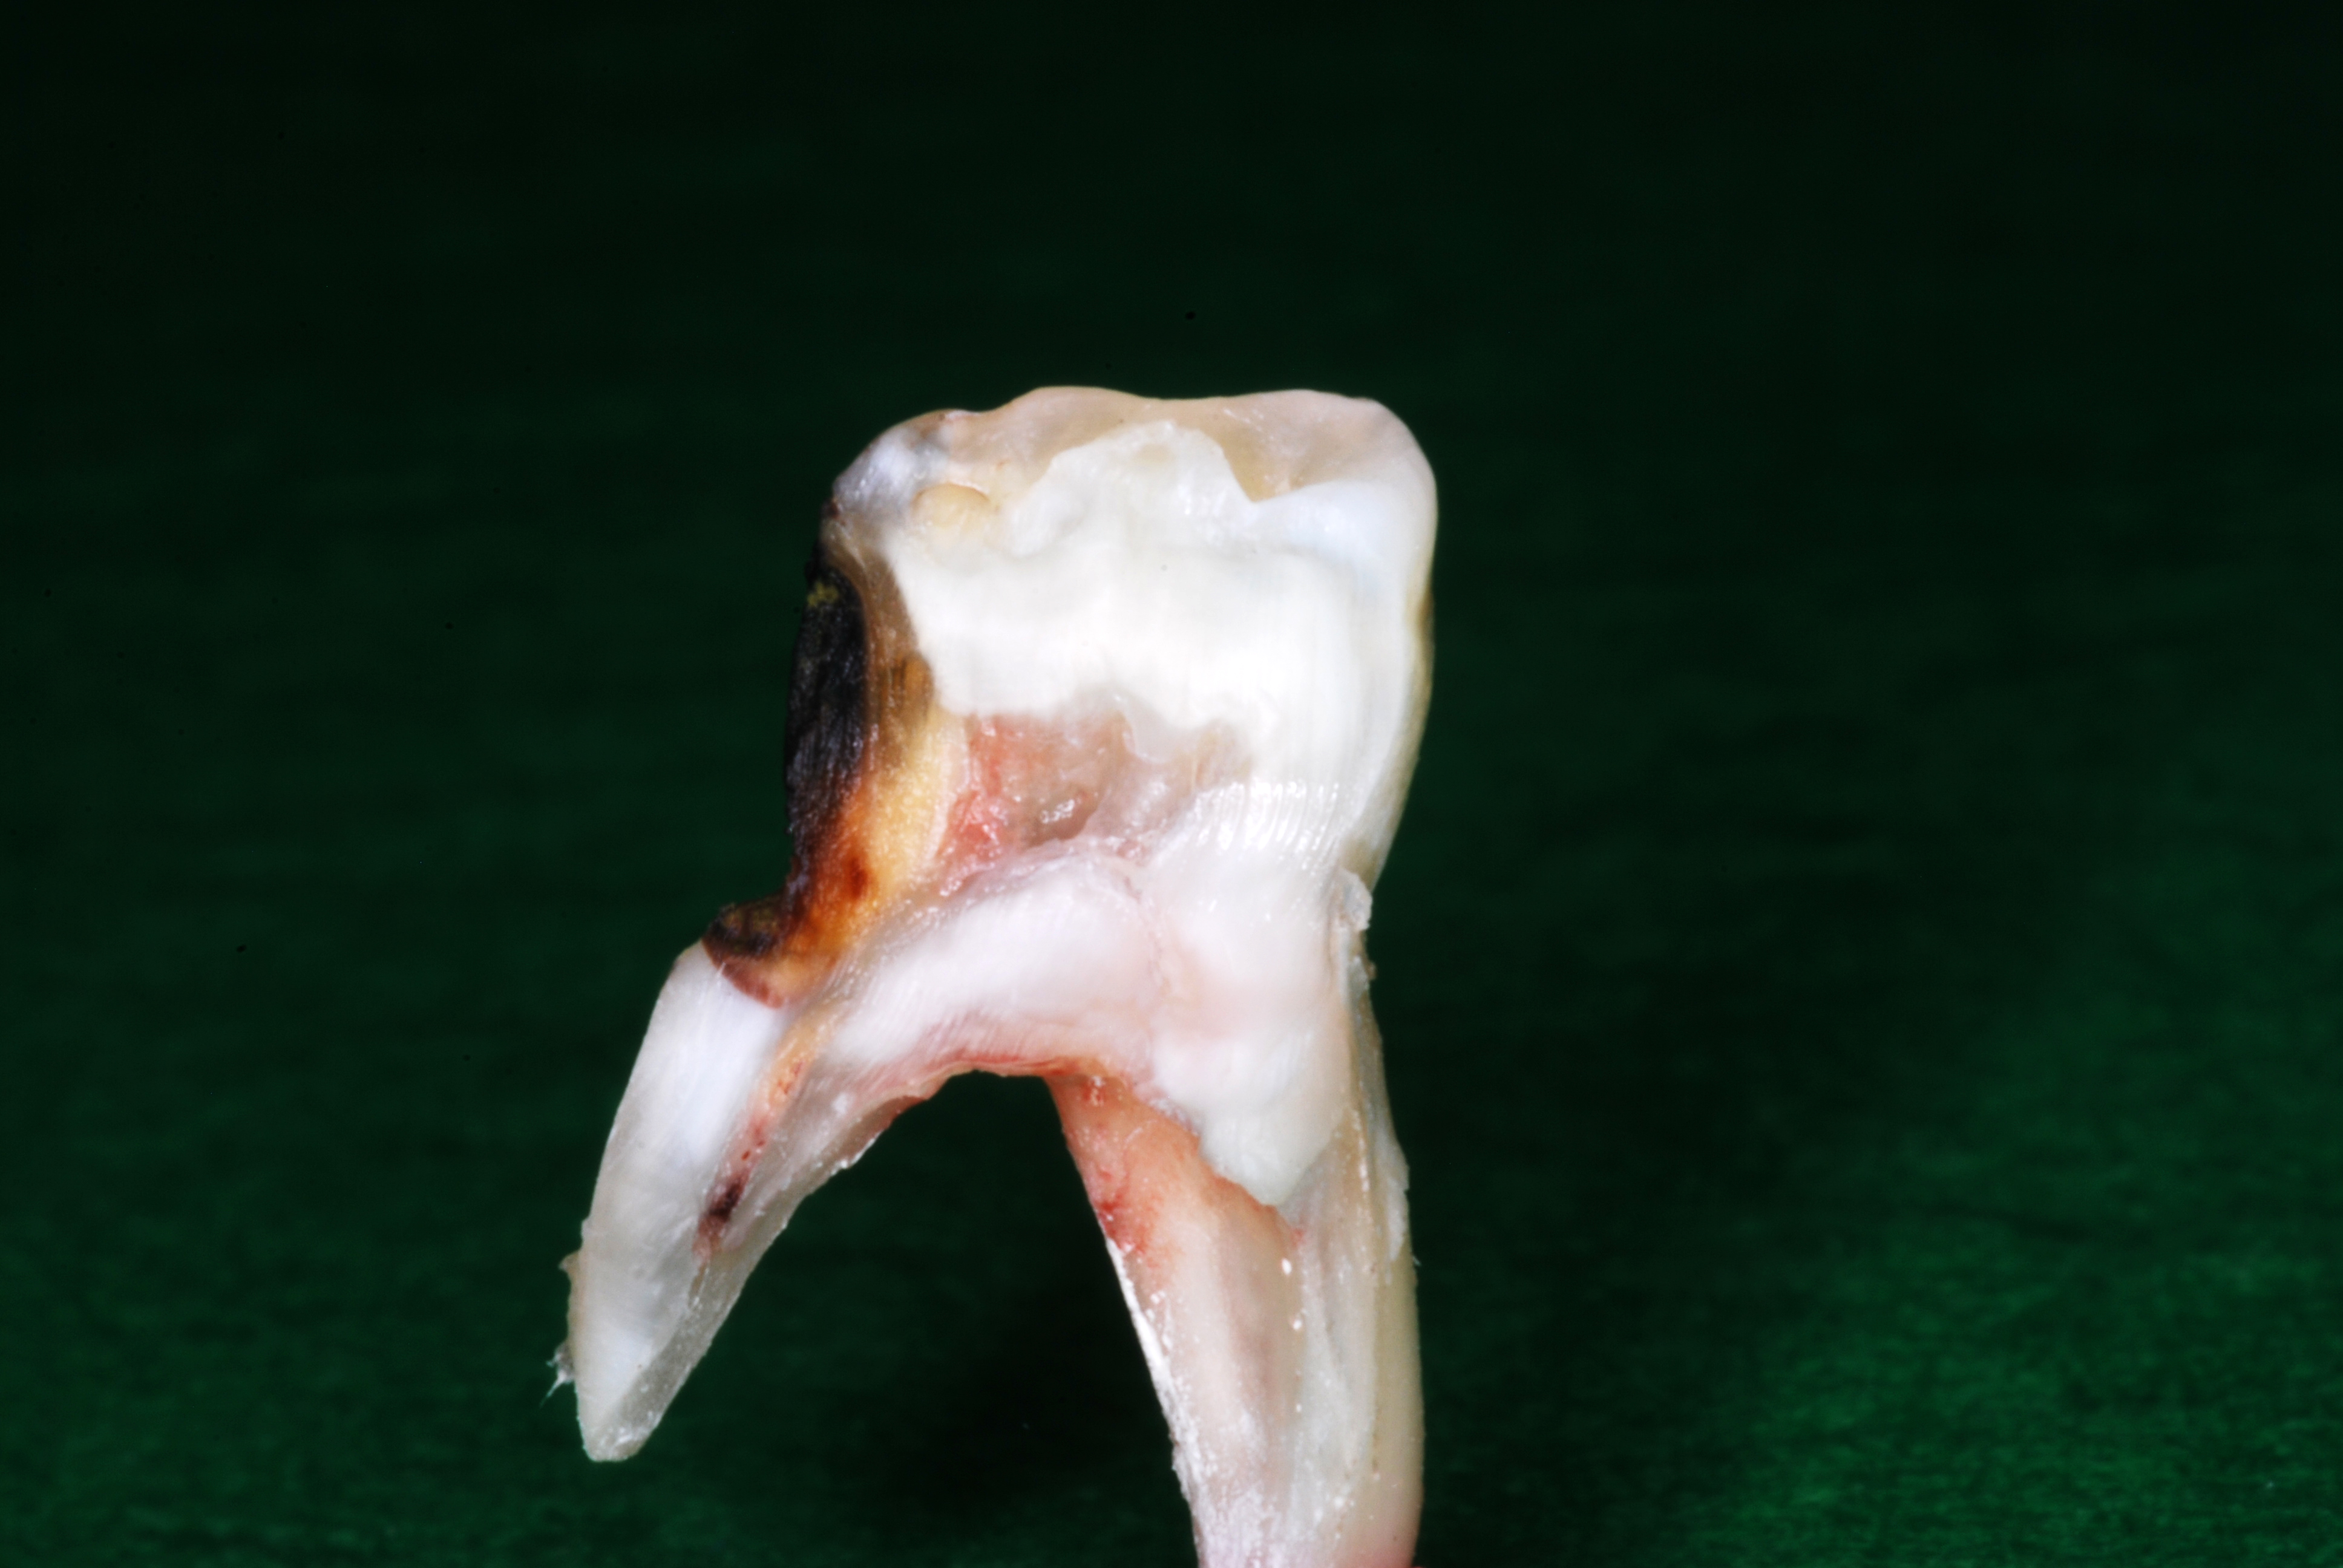

(11.) Views of sectioned primary molar that was extracted for orthodontic considerations 22 months after three SDF treatments that were each 6 months apart.

Figure 11

(12.) Views of sectioned primary molar that was extracted for orthodontic considerations 22 months after three SDF treatments that were each 6 months apart.

Figure 12